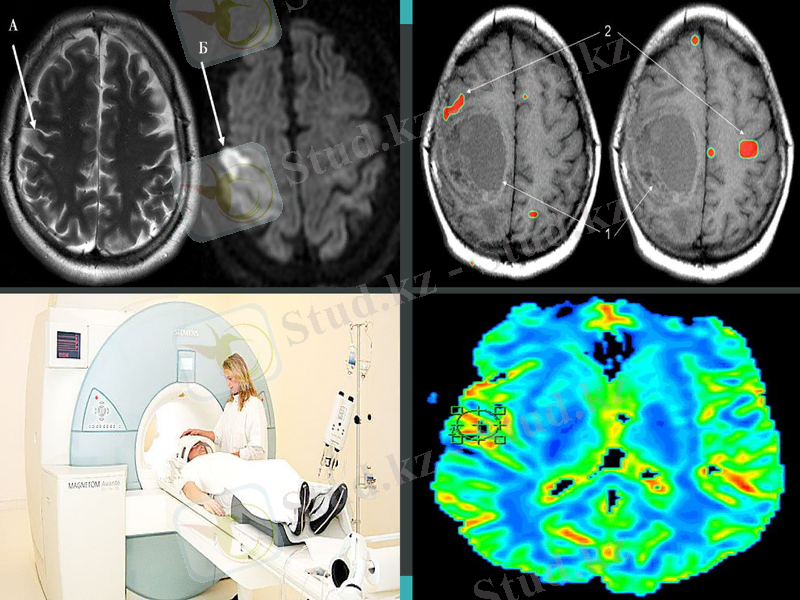

МРТ - динамикалық түрде дамып келе жатқан сәулелендіруші диагностиканың бір түрі. Бұның ескі атауы “ЯМР томография” деп аталады. МРТ- жоғарғы дәрежелі жіңішке - жұмсақ контраска ие және пациенттің кез-келген анатомиялық ерекшелігіне байланысты зерттеу жүргізе алады. Сонымен қатар МРТ инвазивті емес диагностиканың ерекше және жалғыз тәсілі болып табылады. Ол арнайы сезімтал болып келеді және МРТ арқылы сүйек тканьдерінің ісігін және инфильтрациясын анықтауға болады.

Ең алғаш рет МРТ бас миын зерттеулерде қолданылды, ол неврологияның әрі қарай дамуына септігін тигіді. МРТ арқылы жасуша мембранасындағы молекулалардың қозғалысын бағалауға болады(Диффузионная МРТ ), капилляр арқылы қанның жылжуын, метаболиктердің концентрациясын анықтауға болады(Перфузионная МРТ ) . Функционалды МРТ арқылы қозғалыс және сөйлеу орталығын анықтауға болады. Ишемиялық инсультқа ие науқастың МРТ ми инфарктысының алдын ала бола ма жок па болжам жасай алады.